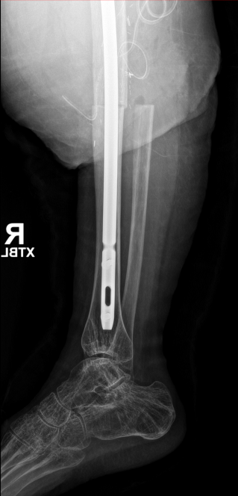

Case presentation: 70 yo F presents to clinic s/p short CMN of left intertroch fx at outside facility in Aug 2022 with worsening left hip pain, inability to bear weight. No pertinent PMHx. Workup and treatment plan?

9

Infxn workup negative, Lateral approach used, Wagner osteotomy to facilitate nail removal, autograft from femoral/neck 50 cc allograft to graft defect in posterior column, multihole cup/screws w/ dual mobility, modular fluted tapered stem.

1

ETO was performed 15cm in length, Cables were deeply imbedded in bone and had to be cut through with ETO, trephine over the remaining distal stem. Revised to modular fluted tapered stem.

2